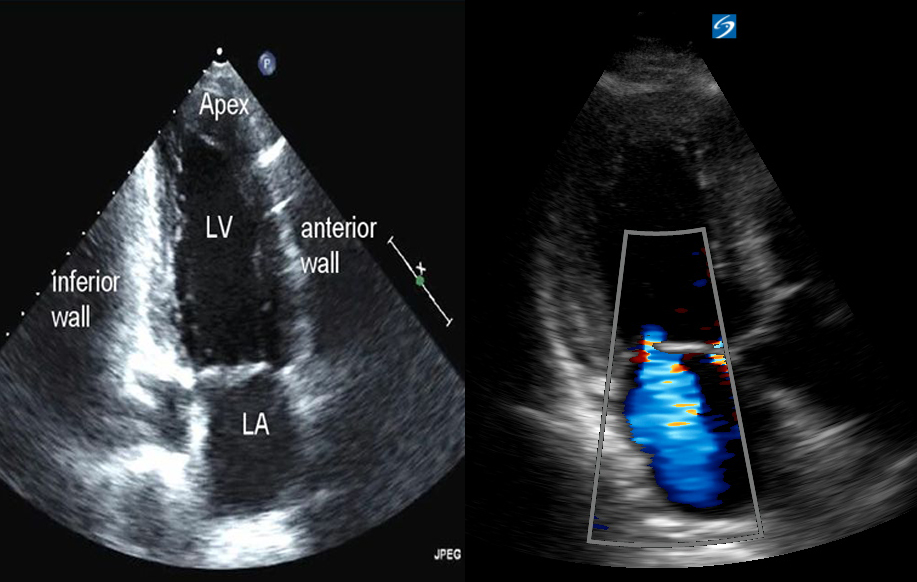

- Mặt cắt từ mỏm: Mặt cắt này khó phát hiện trong siêu âm tim cơ bản. Kỹ thuật này cho phép so sánh kích thước của buồng thất và đánh giá các bất thường về vận động ở thành tim và vùng vách liên thất.

- Mặt cắt cạnh ức: Các vị trí siêu âm ở mặt cắt để đánh giá thất trái và so sánh kích thước của buồng tim. Mặt cứt này cũng giúp phát hiện vấn đề tràn dịch màng tim, tràn dịch màng phổi.